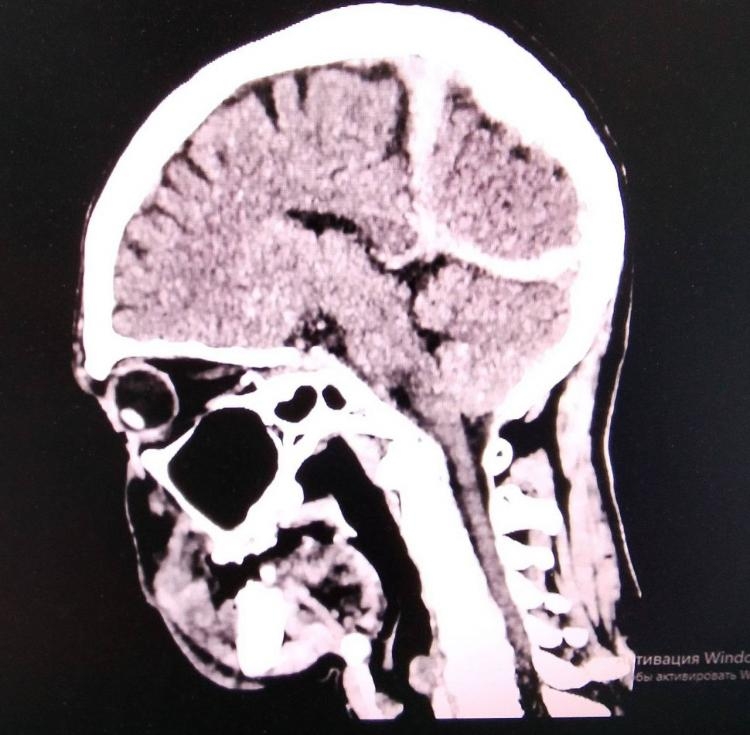

Пострадавший получил тяжелые травмы головы и сильное переохлаждение, но медикам удалось стабилизировать его состояние